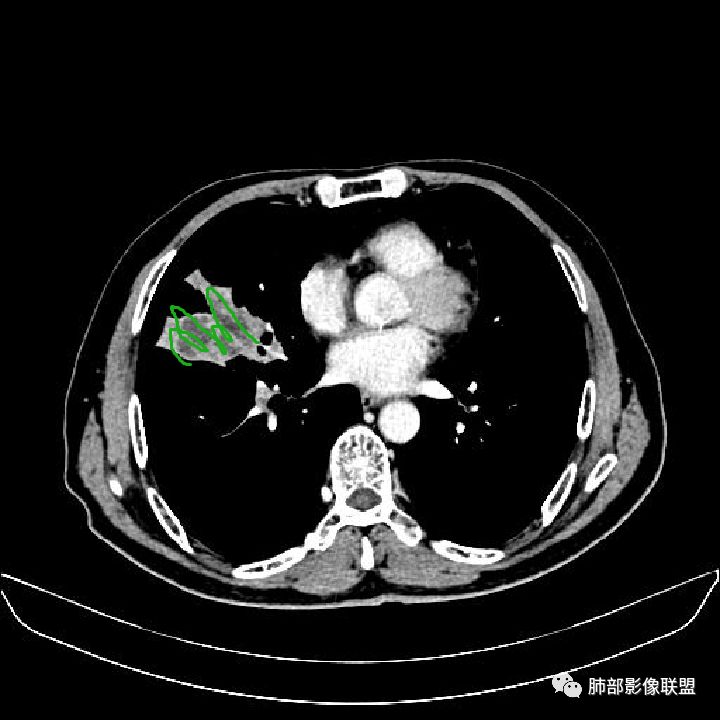

住院4天后行胸部增强CT

静脉期

现在小编来增加一个炎性另一个征象,是我们王兆宇老师原创的----就是墨西哥仙人掌征。

墨西哥仙人掌征---结核        影像上结核灶,粗大的均匀枝干,推测是支气管囊状扩张引起的,在非支气管区,形成圆形坏死囊群;如果这些坏死比较稀薄,又遇到扩张支气管,就会形成粗大的“墨西哥仙人掌”。结核引起的支气管近端炎症纤维化,可以造成支气管阻塞,从而将干酪样坏死物封堵在管腔内。仙人掌主干内部应该是干酪为主,稀薄的,具有流动性,时间久了会出现钙化。

结核坏死与鳞癌鉴别有一点是结核坏死没有方向性,鳞癌有。鳞癌靠近支气管近端部分,血供容易维持,不易坏死,所以坏死靠外侧。而结核干酪样坏死,把一定体积的流动性坏死物,包裹起来,什么形状最省料?坏死物包裹,表面积最省的自然是圆球形,而遇到支气管,坏死物一多,就把支气管撑大了。包裹物是就地取材,扩张的支气管就成了包裹结构。